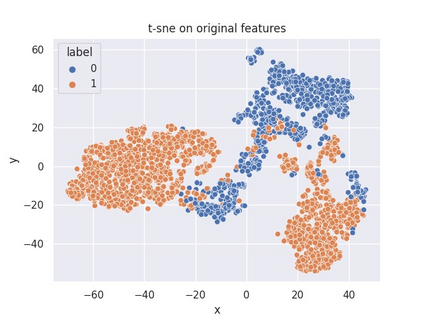

Multiple instance learning (MIL) is a powerful approach to classify whole slide images (WSIs) for diagnostic pathology. A fundamental challenge of MIL on WSI classification is to discover the \textit{critical instances} that trigger the bag label. However, previous methods are primarily designed under the independent and identical distribution hypothesis (\textit{i.i.d}), ignoring either the correlations between instances or heterogeneity of tumours. In this paper, we propose a novel multiplex-detection-based multiple instance learning (MDMIL) to tackle the issues above. Specifically, MDMIL is constructed by the internal query generation module (IQGM) and the multiplex detection module (MDM) and assisted by the memory-based contrastive loss during training. Firstly, IQGM gives the probability of instances and generates the internal query (IQ) for the subsequent MDM by aggregating highly reliable features after the distribution analysis. Secondly, the multiplex-detection cross-attention (MDCA) and multi-head self-attention (MHSA) in MDM cooperate to generate the final representations for the WSI. In this process, the IQ and trainable variational query (VQ) successfully build up the connections between instances and significantly improve the model's robustness toward heterogeneous tumours. At last, to further enforce constraints in the feature space and stabilize the training process, we adopt a memory-based contrastive loss, which is practicable for WSI classification even with a single sample as input in each iteration. We conduct experiments on three computational pathology datasets, e.g., CAMELYON16, TCGA-NSCLC, and TCGA-RCC datasets. The superior accuracy and AUC demonstrate the superiority of our proposed MDMIL over other state-of-the-art methods.